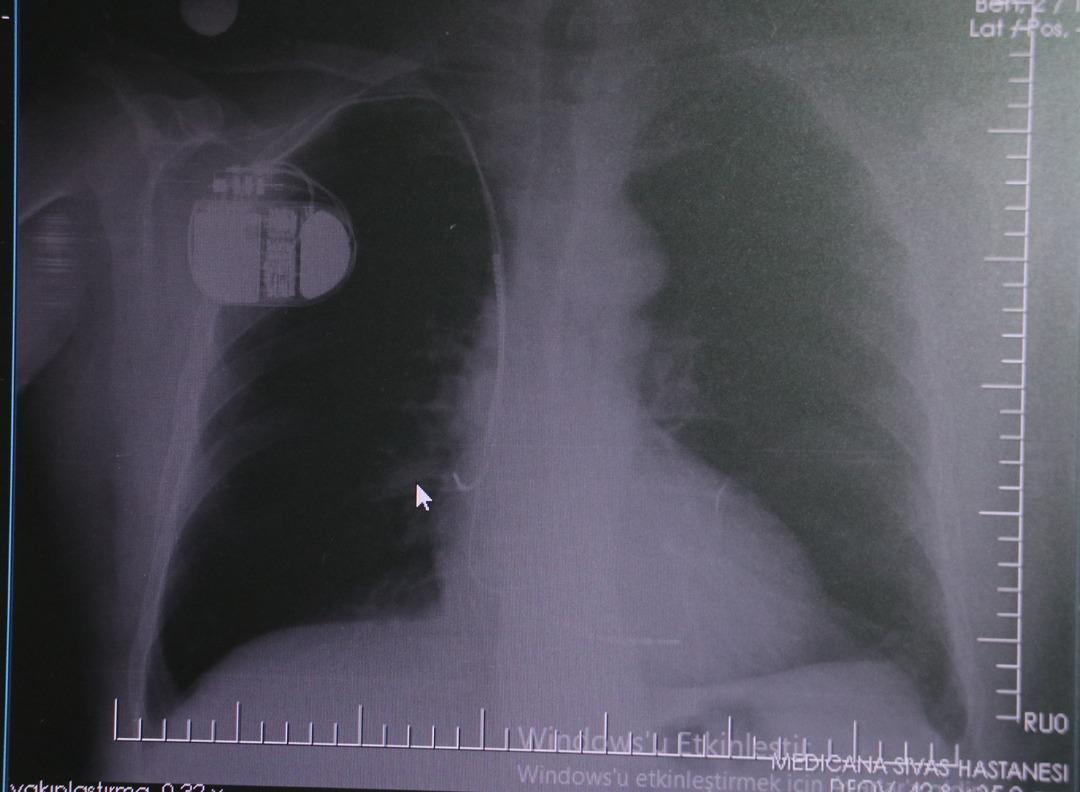

Konuya ilişkin açıklamalarda bulunan Kardiyoloji Bölümü Uzmanı Dr. İsmail Erdoğu, kalp pilinin önemine vurgu yaptı. Erdoğu, Yeni nesil kalp pillerinin MR cihazlarına girmeye imkan sağladığı, ancak tarama cihazlarından geçmenin önerilmediğini ifade ederek, "Soğuk hava nedeniyle oluşan titremeler, kalp pilinin kalbin durduğunu sanmasına ve yanlış şoklamaya yol açabilir. Bu nedenle hastalarımızın bu dönemlerde daha dikkatli olmalarını öneriyoruz" dedi.

Kalp krizleri sonrası kalp dokusunun zarar gördüğünü söyleyen İsmail Erdoğu, "Dünyada artık kalp hastalıkları en sık ölüm sebeplerinden biri. Kalp hastalıklarında çok fazla grup var. Biz kalp hastalıkları deyince sadece kalbinde stent olan ve damarlarında sorun bulunan insanlardan bahsetmiyoruz. Aynı zamanda tansiyon ve şeker hastaları da kalp hastalıklarına aday. Toplumun yaklaşık yüzde 30-35'lik bir kısmını kapsıyoruz. Çok yaygın bir hastalık ve bu hastalıkta teknolojik kapsamda, ilaç konusunda son 30 yılda çok ciddi gelişmeler oldu. Geçmişte insanları hastanelerde kalp krizinden dolayı kaybederken şimdi hastaneye başvurular sonrasında yaşama tutunmak büyük oranda mümkün. Yaşanan ölümler ise genellikle hastaneye gelmeden önce gerçekleşmekte. Kalp krizinden kurtulmanın hastalarda belli bir bedeli oluyor. Kalp krizi sonrası kalpteki dokular zarar görüyor ve kalp yetersizliği oluşuyor. Bu kalp yetersizliği olan kalplerde ritim bozuklukları ve ani ölümler gibi sorunlar gündeme gelebiliyor. Bunlardan uzun vadede korunmak için hastalarda mutlaka bir kalp piline ihtiyaç duyuluyor" dedi.

Kalp pilleri ile MR cihazına girilebileceğini belirten Erdoğu, "Çok büyük bir ameliyat değil ama yine de ciddi bir cerrahi işlem. Kalp pili, tıpta son 30 yılda yaşanan gelişmelerden en büyüğü. Bir bilgisayarın küçültülüp insan vücuduna konulmuş hali aslında. İnsan ömrünü ciddi oranda uzatan bir tedavi. İnsanlar bir şokla hayata tutunurken, pil olmasaydı öleceğini düşündüğümüz birçok hastamız var. Kalp pilinin bu özelliği, uygun hastalarda ciddi oranda ani ölümü engelliyor. Hastanın başına gelecek bir kalp durması durumunda yanında bir sağlıkçı yoksa, onun ritmini düzeltecek defibrilatör cihazı yoksa hastayı hayatta tutmak mümkün değil. Uygun endikasyonlarda kalp pili olduğu zaman, pil hastaların ritmini algılıyor ve acilde yapılan şoklamayı yaparak hastayı hayata döndürüyor. Kalp pillerinde yeni teknolojilerle MR'a girmek mümkün, tomografiye zaten girebiliyorlar. Tarama cihazlarından geçmelerini uygun görmüyoruz. Bu tarz durumlarda hastalarımız 'kalp pilim var' dediğinde muaf tutuluyorlar. Kalp pilleri ciddi teknolojik cihazlardır. Vücudun içindeki titreşimi, örneğin mikser kullanmak, kolunu sallayacak herhangi bir eylem kalp pilinde olumsuz etki oluşturabilir. Soğuk havalarda vücutta oluşan ciddi titremeler kalp pilinin hafızasını karıştırıp kalbin durduğunu düşündürebilir ve gereksiz şoklama yapabilir. Bu tarz kişilerin soğuk havalarda daha temkinli olması gerekir" dedi.